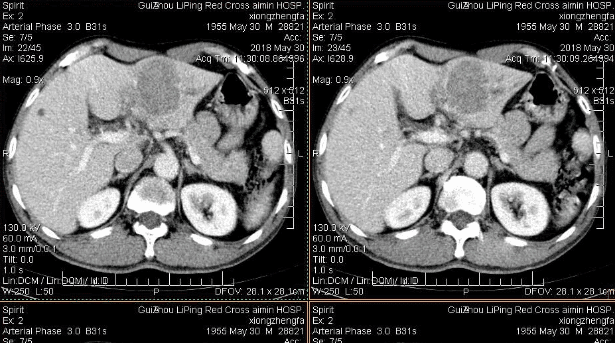

小荆挂着焦急的脸庞 , “肝癌?!医生 , 是不是搞错了 , 我怎么可能得肝癌呢?”

【金兰中医学社|?37岁男子频繁乏力,确诊肝癌,医生咆哮:身体早有反常,却被他忽视】小荆转头去找了肝病科的主任 , 在病房里呆了大半天 , 才满脸痛苦的出来 , 下楼梯的时候最终没有忍住 , 留下了眼泪 。

刚才主任说 , 看你还曾有过轻度肝硬化的诊断记录 , 最近身体有多处异常表现 , 都不见你来医院检查 , 延误病情 , 这才是真正导致肝脏最终癌向发展的原因 。